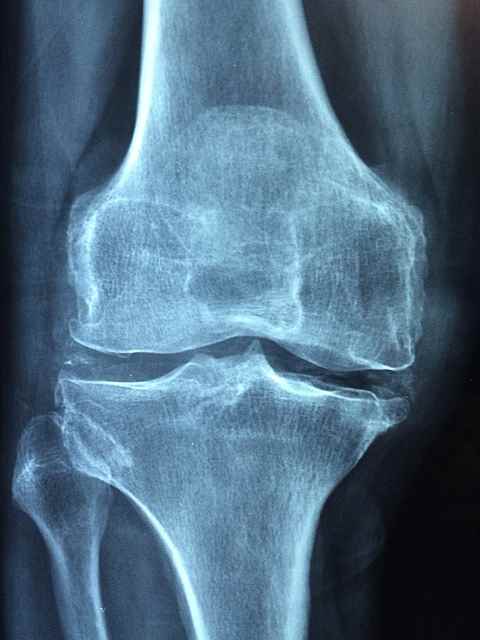

3. 류마티스 관절염

류마티스 관절염은 골관절염과 달리 무릎을 포함한 관절에 염증이 생기는 자가면역질환입니다. 질환은 치료하지 않고 방치하면 관절 손상과 기형으로 이어져 통증이 지속되고 이동성이 제한될 수 있습니다.

류마티스 관절염